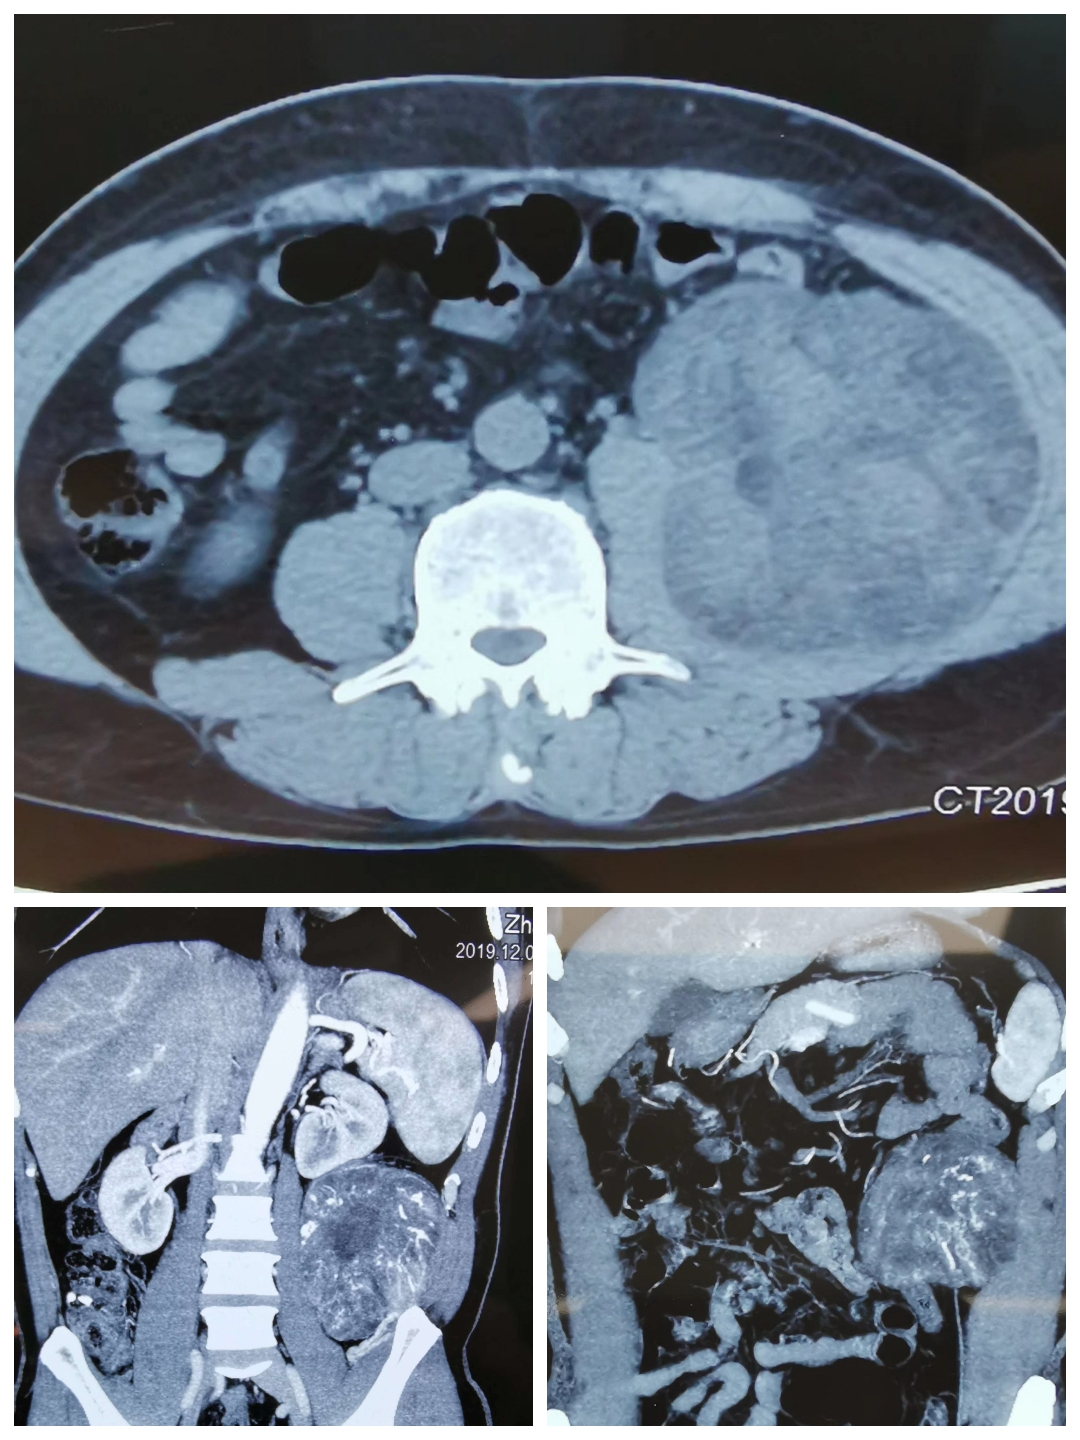

2019年12月22日,是我国传统二十四节气中的冬至,在家家户户团聚在一起包饺子、吃饺子之际,秀人网 外二科(结直肠肛门疾病专业、综合外科)在麻醉手术室、检验科等相关兄弟科室的配合下,成功完成一例腹膜后巨大肿瘤切除术。患者男性,主因“左侧腹部憋胀不适6月”而入院。完善腹部CT回报:左中腹部腹膜后巨大占位性病变,考虑脂肪肉瘤可能性大。患者近期有发热表现,不排除肿瘤出血、坏死可能。经过充分的术前评估,翟春宝主任决定限期行根治性手术治疗。

手术标本,大小约13cm×13cm×15cm,包膜完整,脂肪肉瘤可能